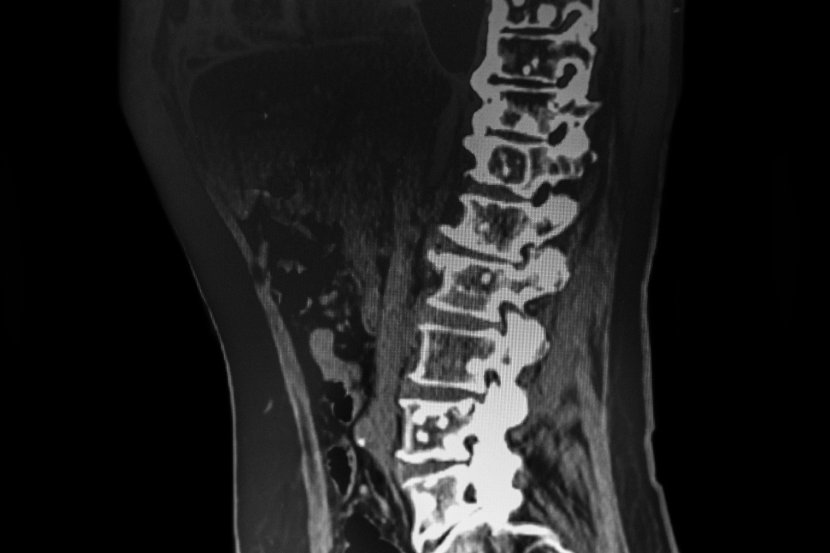

Metastaze na kostima nastaju kada se ćelije primarnog karcinoma prošire na delove skeleta. Mogu da izazovu mnoge probleme kao što su bol, lom kosti ili ozbiljnije komplikacije. Najčešće mesto na kome se pojavljuju metastaze na kostima jeste kičma.

Gotovo svi karcinomi se mogu proširiti na kost, a maligniteti sa kojih najčešće ide širenje na kosti su na dojci, plućima, prostati, bubrezima, melanomi, jajnici i štitasta žlezda. Iako je kičma najčešće mesto na kome se javljaju metastaze na kostima, uobičajena mesta su i kost kuka (karlica), kost natkolenice (femur), kost nadlaktice (humerus), rebra i lobanja. Kosti inače sačinjavaju dve vrste koštanih ćelija:

Metastaze u kostima mogu izazvati i druge probleme. Kada se rak proširi na kosti kičme, može pritisnuti kičmenu moždinu. To može izazvati oštećenje nerva koje, ukoliko se ne leči interventno, ponekad dovodi do paralize. Ako se previše kosti razgrađuje, kalcijum se oslobađa u krv. Ovo stanje potencijalno dovodi do posledica uzrokovanih visokim nivoom kalcijuma u ​​krvi (hiperkalcemija).

Prelomi se mogu desiti pri padu ili povredi, ali se slaba kost takođe može slomiti tokom normalnih aktivnosti. Prelomi se najčešće dešavaju u dugim kostima ruku i nogu i kostima kičme, uz veliki, iznenadni bol. Iznenadni bol u sredini leđa, na primer, može značiti da je slomljena kost u kičmi.

Kada je to moguće, lekari će pokušati da spreči prelom. Mogu se davati lekovi za jačanje kostiju koji bi trebalo da pomognu u sprečavanju preloma. Ako rendgenski snimak pokaže da je kost ruke ili noge slomljena, može se uraditi operacija sa ugradnjom metalnih šipki u deo kosti ili hirurška intervencija kako bi se preko slomljenog dela kosti stavio čelični nosač. Ako se kosti kičme lome, koristi se koštani cement (vertebroplastika ili balon kifoplastika). To će pomoći u jačanju i stabilnosti kompletnog skeleta.